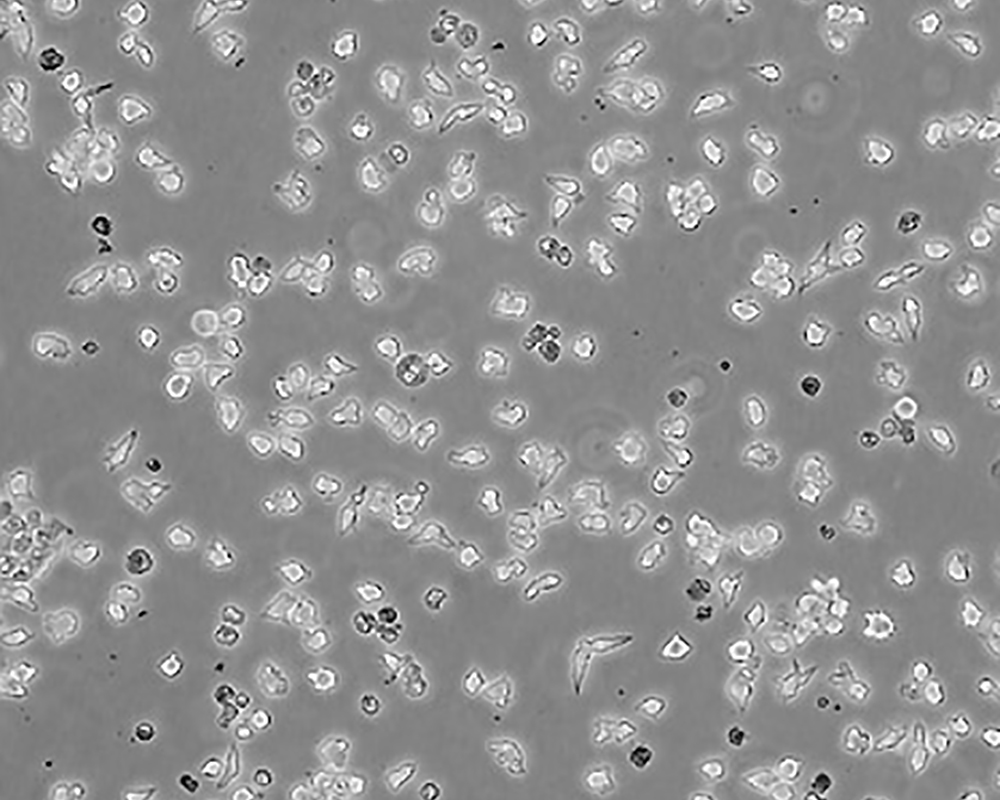

中文名稱 小鼠淋巴瘤細胞

組織來源 淋巴瘤; C57BL/6N

細胞種屬 mus musculus, mouse

生長特性 suspension

形態(tài)特征 lymphoblast

細胞描述 EL4是從用9,10-二甲基-1,2-苯并蒽在C57BL小鼠中誘導的淋巴瘤中建立的。 能抗0.1 mM 氫化可的松,對20 mcg/ml PHA敏感。 還有一個亞株(EL4.IL-2, ATCC TIB-181)可以生成高水平的IL-2。 檢測表明肢骨發(fā)育畸形病毒(鼠痘)陰性。